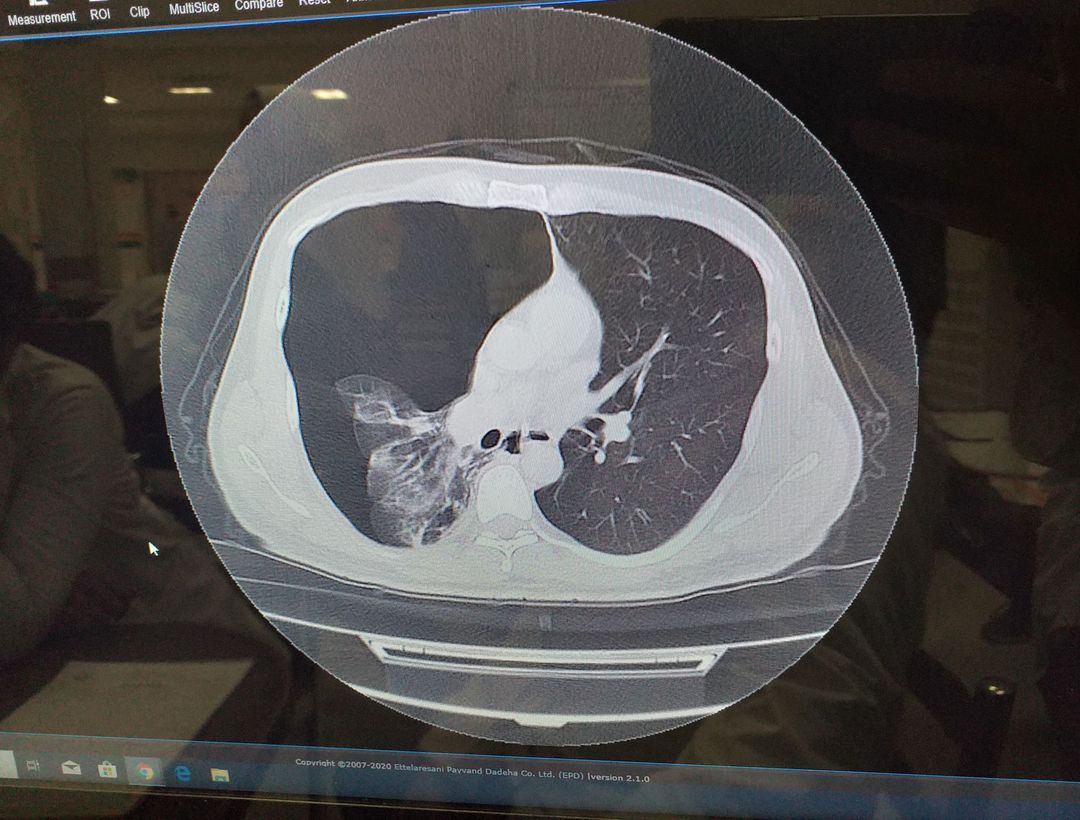

A 28 year male visiting for shoulder pain. He had a history of stretching his arm yesterday and cigarette smoker.

Its pneumothorax he had a bleb that ruptured most probably

Pneumothorax with lung rupture

Right pneumothorax